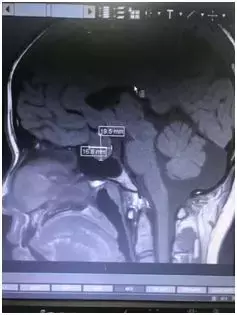

垂体磁共振结果显示,小陈的垂体上有一个大约2.3cm*1.9cm*1.6cm瘤体。

这个小小的瘤就是引起她闭经、泌乳的罪魁祸首。

垂体矢状位图见泌乳素瘤